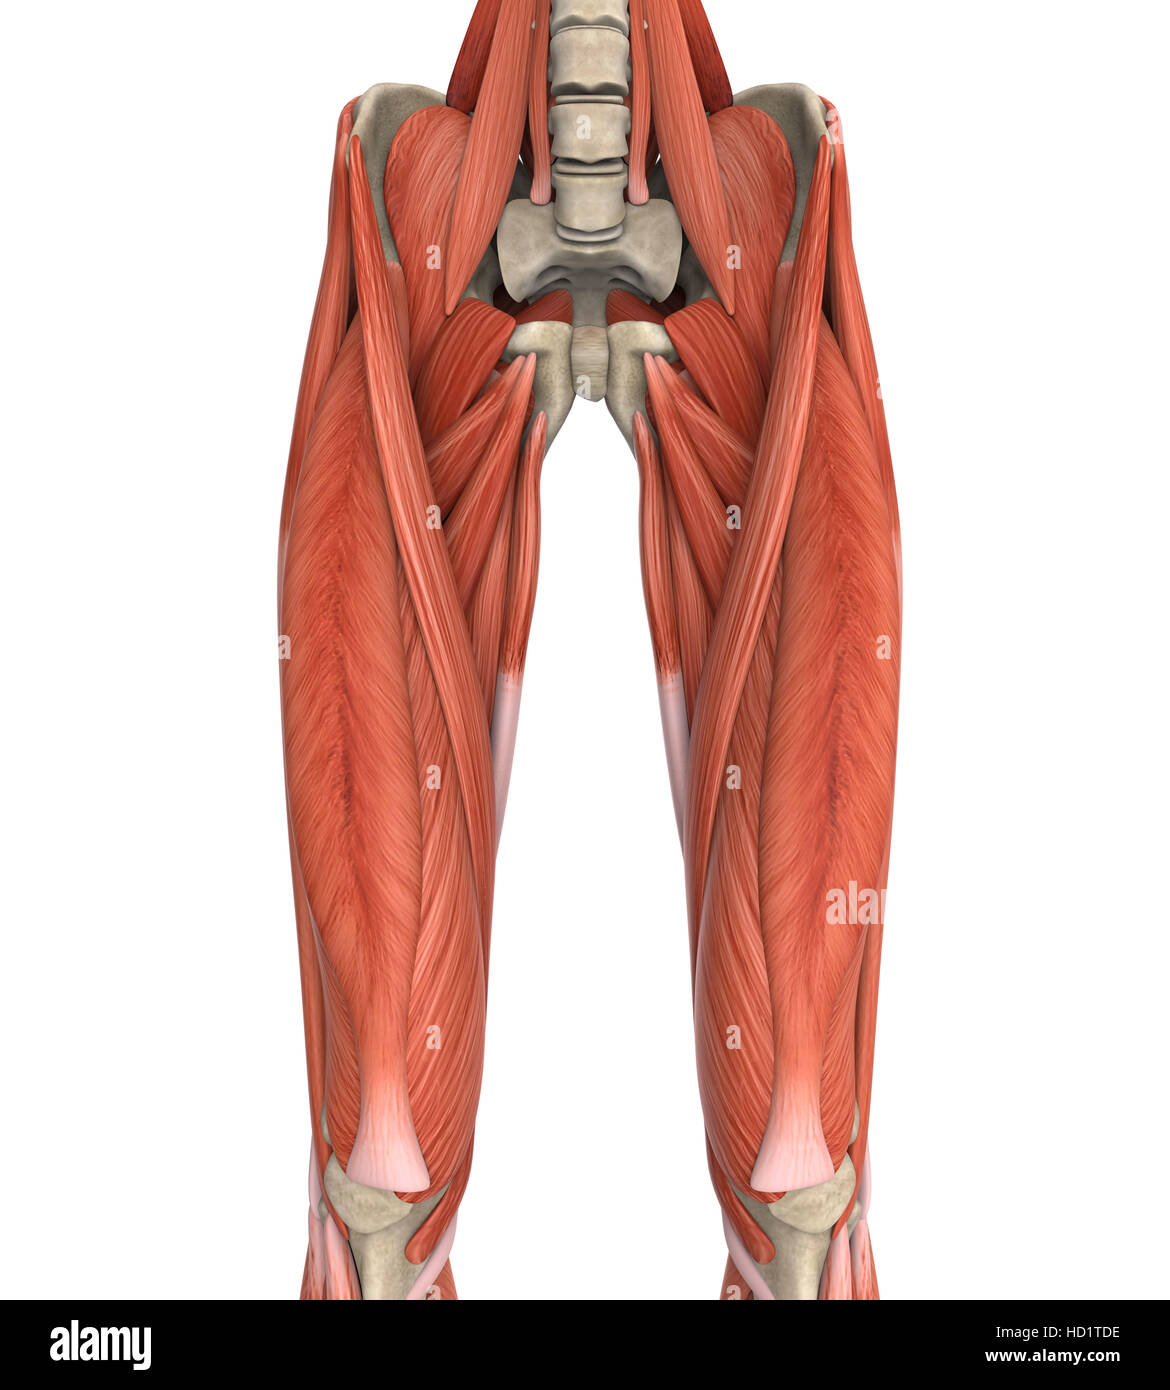

Anatomie des muscles des jambes supérieure Banque D'Imageshttps://www.alamyimages.fr/image-license-details/?v=1https://www.alamyimages.fr/photo-image-anatomie-des-muscles-des-jambes-superieure-128504263.html

Anatomie des muscles des jambes supérieure Banque D'Imageshttps://www.alamyimages.fr/image-license-details/?v=1https://www.alamyimages.fr/photo-image-anatomie-des-muscles-des-jambes-superieure-128504263.htmlRFHD1TDY–Anatomie des muscles des jambes supérieure